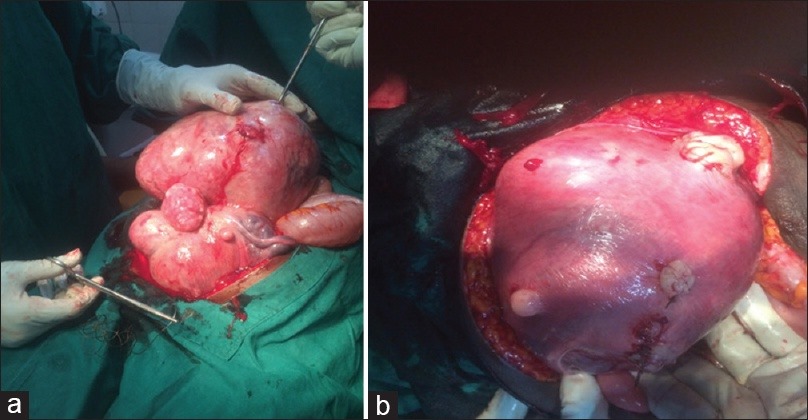

Infertility occurs primarily from the combination of fibroids, ovarian cysts, tubal blockage, and sometimes a hot stomach.

But one common problem with the above is that 90% of the time, the fibroid grows back and stops you from getting pregnant and having your own baby.

For some, a fibroid can even grow to term, and they deliver it.

Which might sometimes lead to:

….Permanent loss of the womb